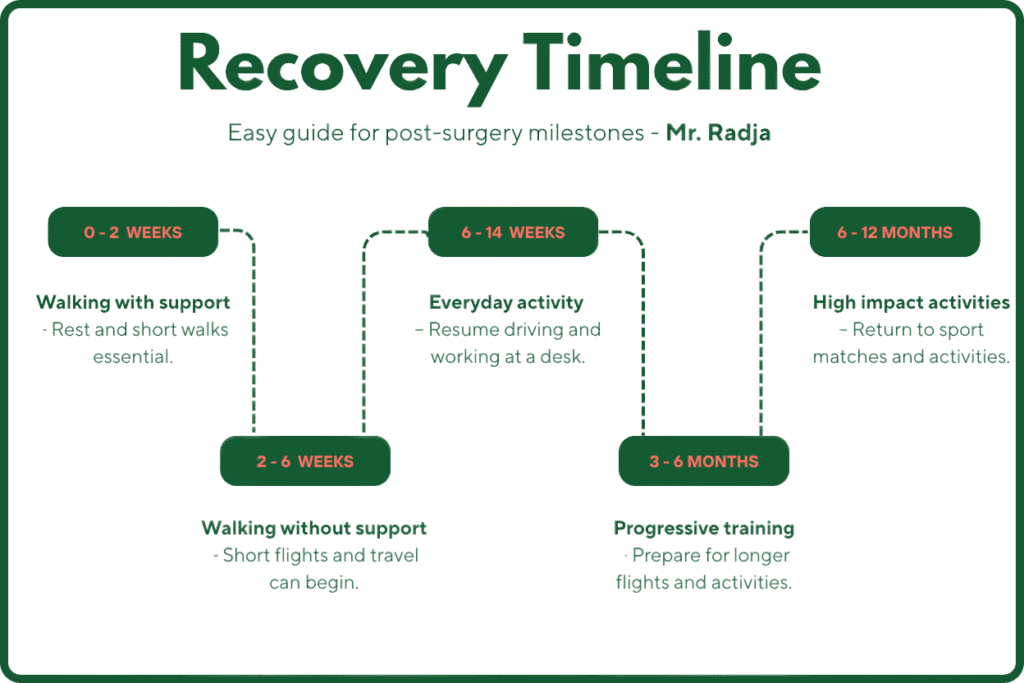

Recovery Timeline

Knee arthritis affects 1 in 5 adults over 45 in England (18.2%), but early diagnosis and treatment can make a real difference. Most people do well with lifestyle adjustments, exercise, and therapy whereas surgery is needed only for a minority.

If you’re in Manchester and suffering knee pain or stiffness, schedule a specialist assessment with Mr. Radja and take the first step toward lasting joint health.